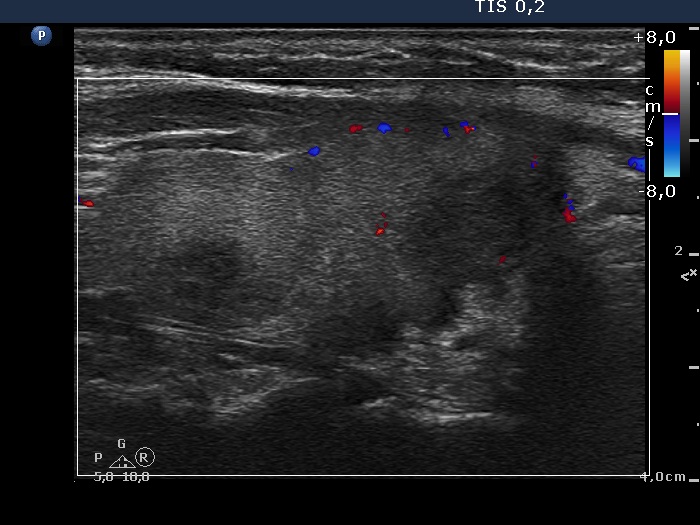

Patient referred for evaluation of thyroid nodule - final diagnosis Hashimoto's thyroiditis - Case 13. (ultrasonographic picture 8)

Right lobe, longitudinal scan, color Doppler mode.